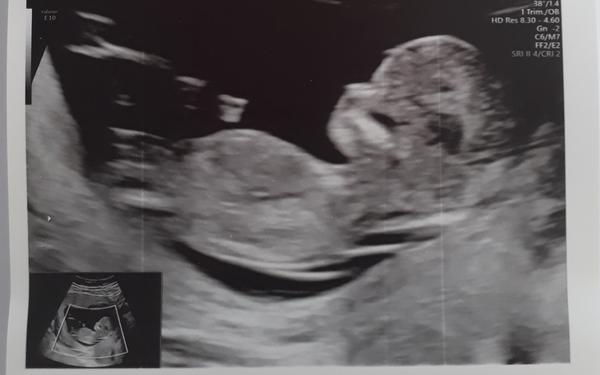

@ivca_ch proč myslíš? Ten UZ se má dělat mezi 12. a 14.tt, to jdeš úplně uprostřed toho rozmezí.😉 mně takto v nemocnici objednali a byla jsem překvapená kolik toho bylo vidět (pan doktor tam prohlížel mozkové hemisféry, oční čočky, srdíčko..)

@pipi_puncocha to je krásná fotka a gratuluji k dobrému výsledku screeningu 😃 dívám se, že máme skoro stejný termín, já mám 15.11😉👍

@lucije66 děkuji. 😍 a tobě moc držím palce na čtvrtek na screening, já jsem noc předtím téměř nespala.🤦♀️

Ahoj holky, také bych se k vám přidala.. podle UTZ jsem 13+4tt, včera screen a vše ok.. dítě se nechtělo doktorovi ukázat v tom nejlepším světle, naštěstí po troše přemlouvání si dalo říct.. nevolnosti už mám snad trvale za sebou, ale jisté nechutenství zůstalo.. prsa občas taky dost cítím, jako by byla plná mlíka :D